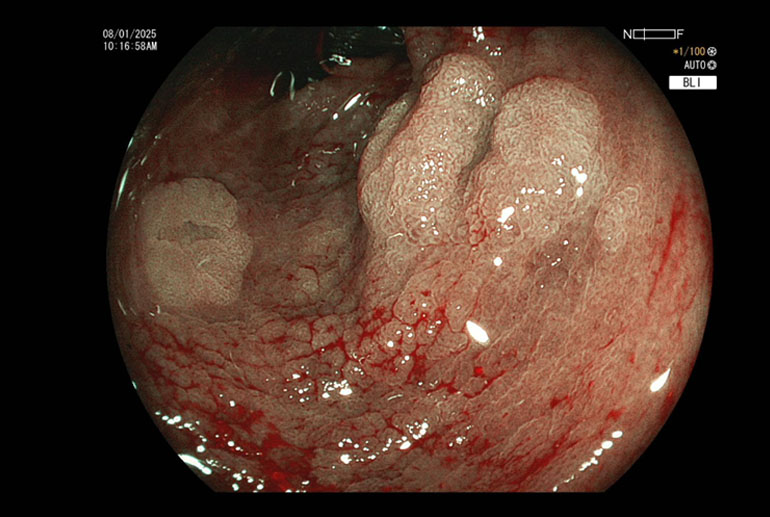

DLMN, F, 50 yrs.Known case of ulcerative colitis for more than 10 years underwent porotocol based surveillance colonoscopy. Multiple flat polyps were encountered in all segments of the colon and a total of 8 polyps were removed using the technique of Underwater Cold Snaring. Patients who have had inflammatory bowel disease for a long time […]